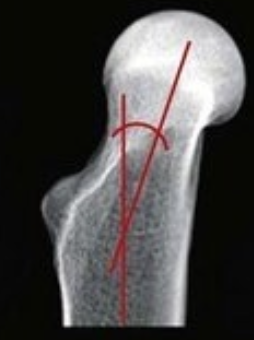

What is this?

angle of inclination

angle of anteversion